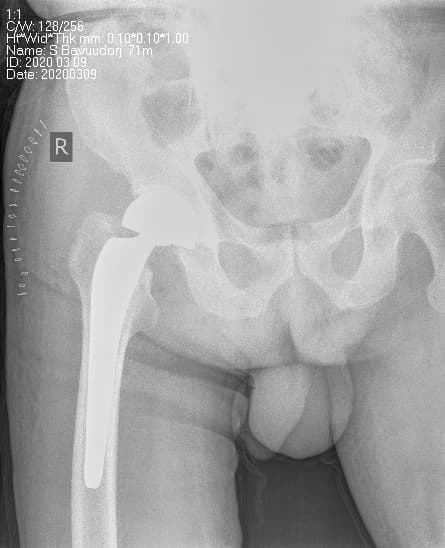

Мэс заслын өмнөх болон дараах рентген зураг